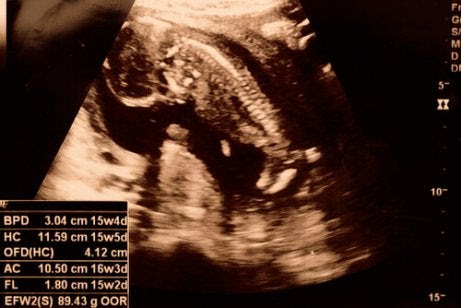

På vissa ultraljudsbilder är det möjligt att bestämma barnets kön så tidigt som vid 15 veckor. Fostrets armar och ben växer och det kan böja sina leder.

Under vecka 15 har inte barnets skelett bildats än. Men du kan se ryggraden och dess nervändar. Dessutom kan fostret höja nacken och händerna. Faktum är att du i vissa fall kan observera att barnet stoppar fingrarna i munnen.